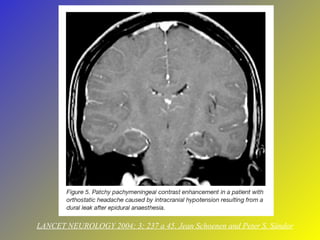

LANCET NEUROLOGY 2004; 3; 237 a 45, Jean Schoenen and Peter S. Sándor